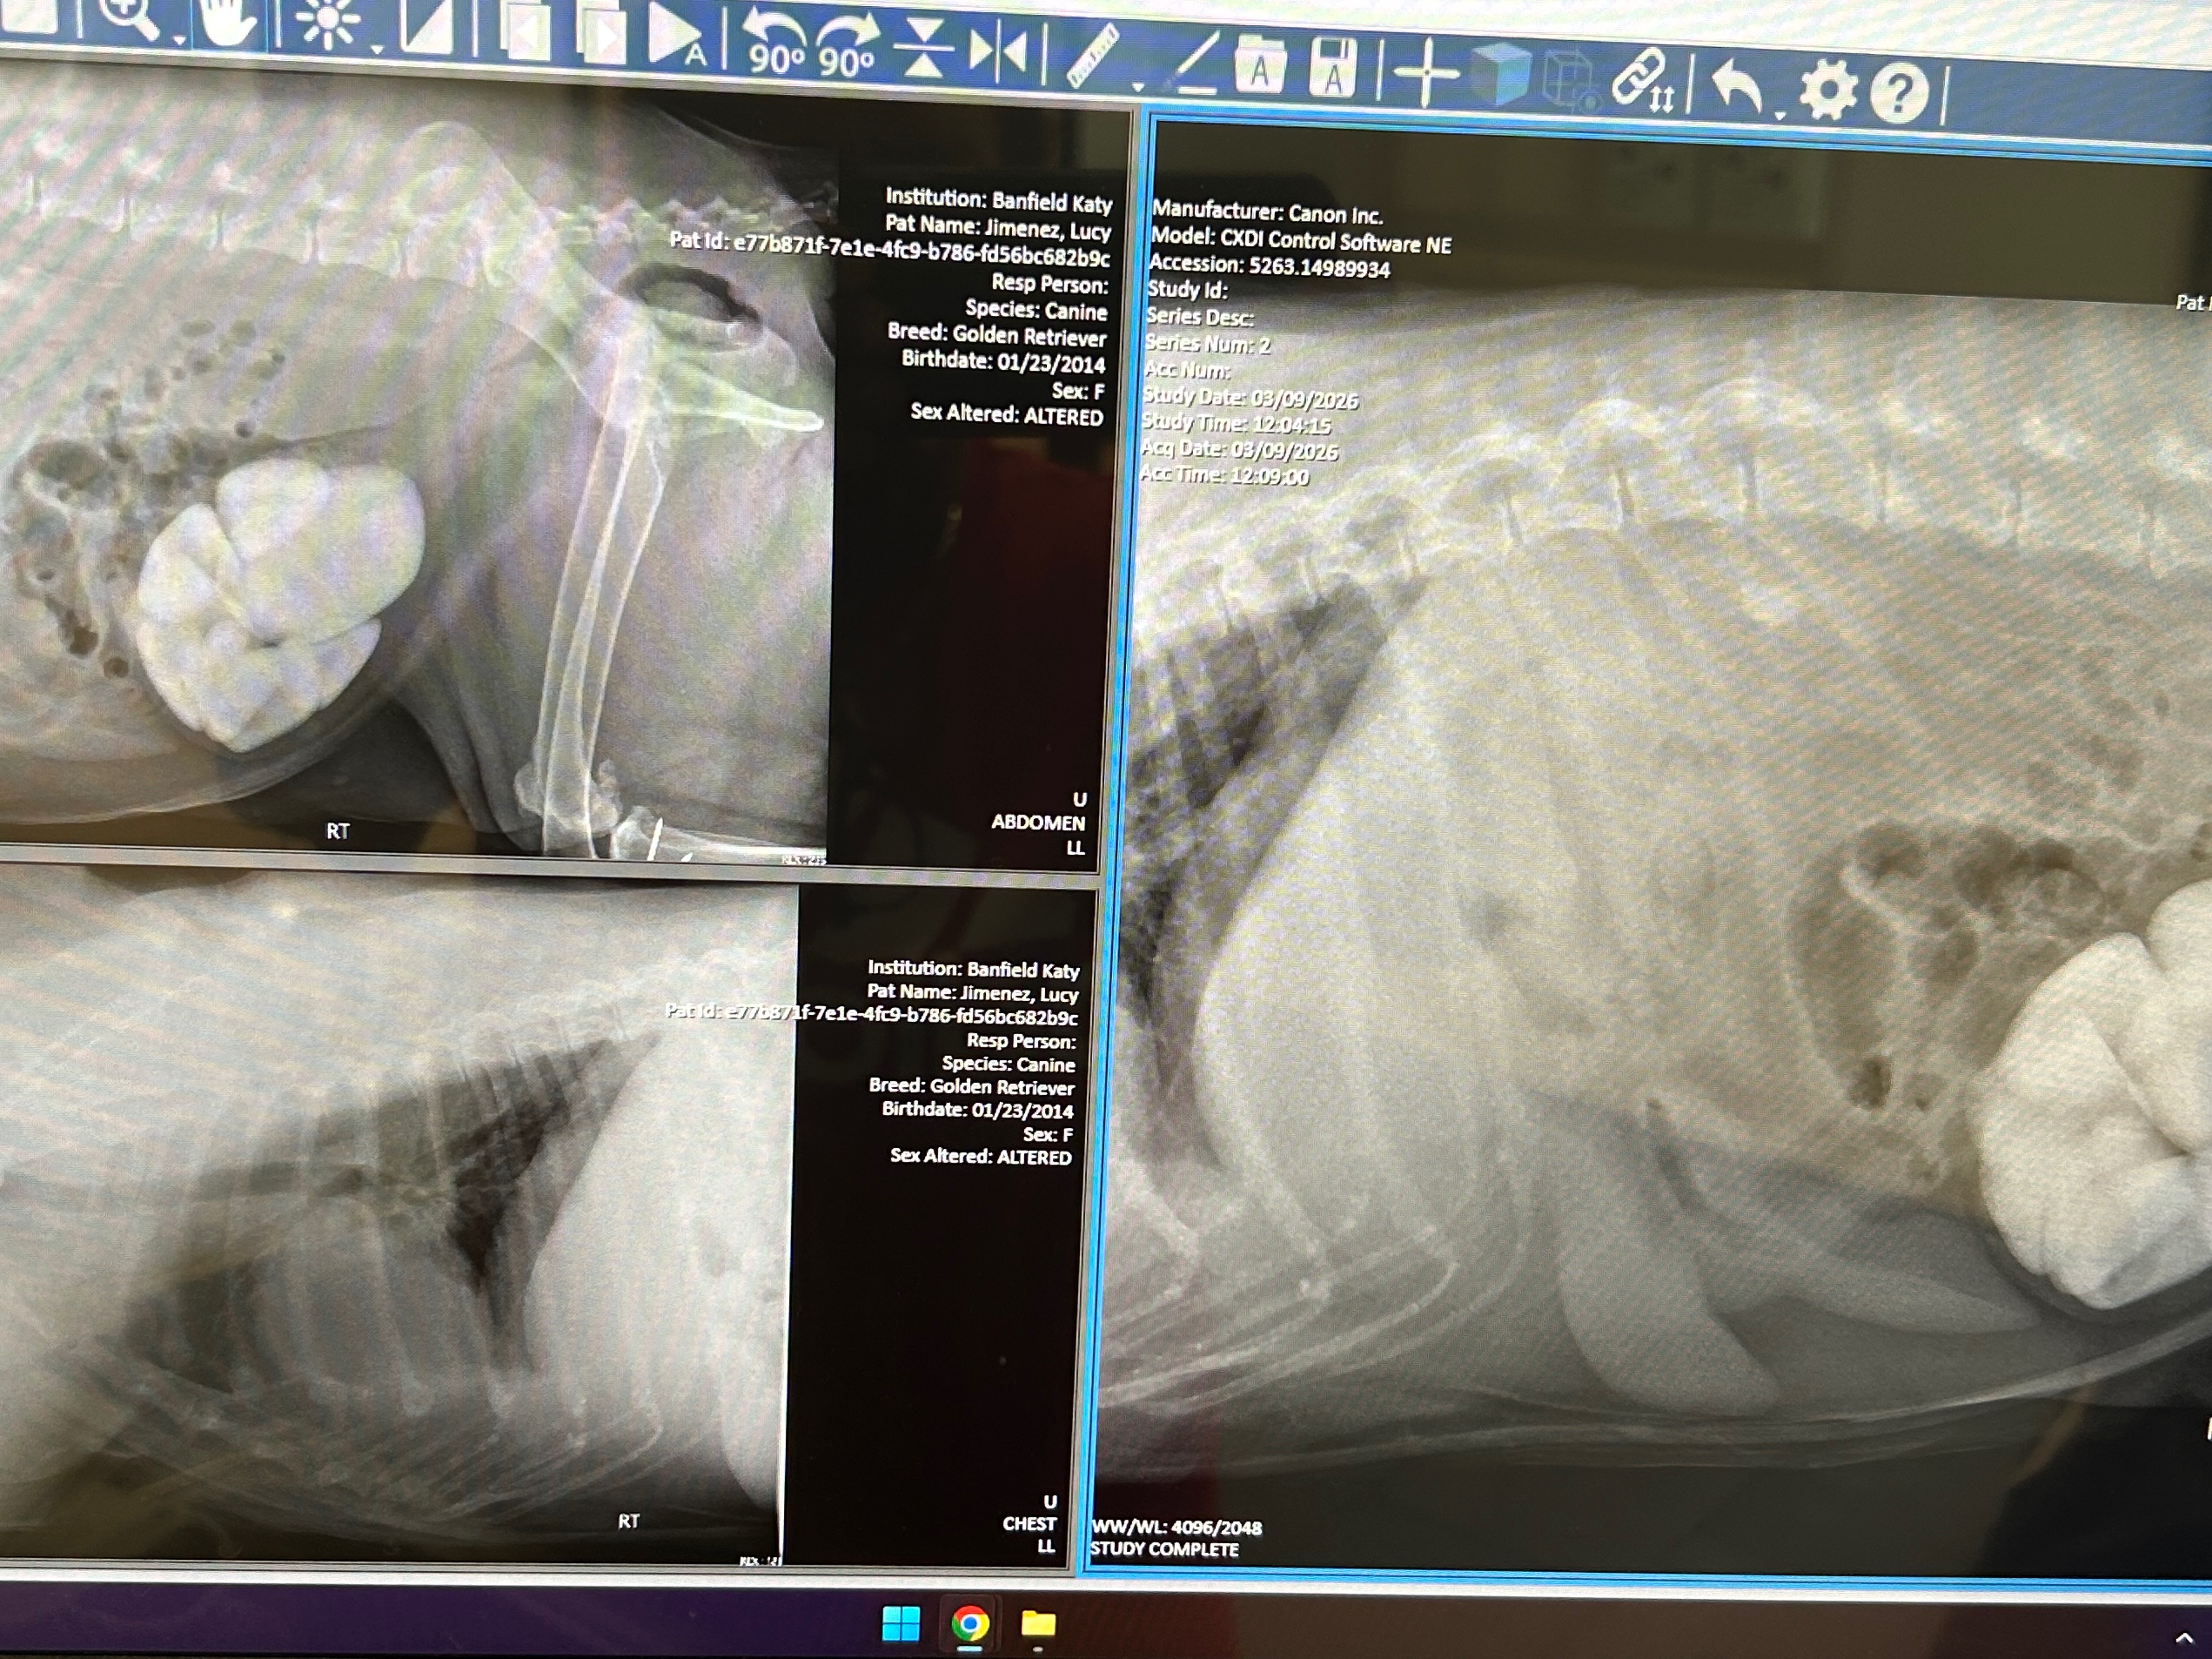

My name is Nancy, and my dog Lucy is truly my best friend and constant companion. She means everything to me—she’s my family, my comfort, and my joy. Recently, Lucy became very sick. I noticed blood in her urine and rushed her to see Dr. Cornelius at Banfield for an evaluation. The veterinarian took the time to explain Lucy’s condition to me, and I learned that she has bladder stones and blood in her urine, which is causing her a lot of pain. It’s even become difficult for her to go to the bathroom, and seeing her struggle breaks my heart.